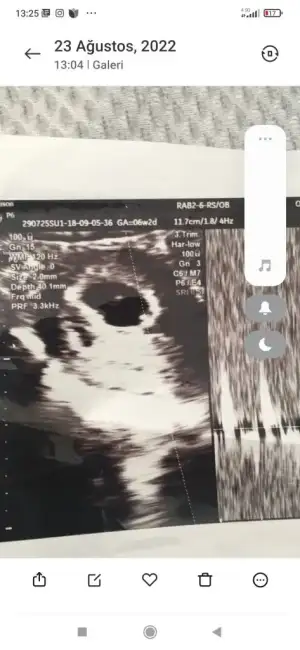

Bakın bunlarda iki kızımın teoriye göre kız değil mi

Eklentiler

• Screenshot_2022-09-16-13-25-00-162_com.miui.gallery.webp

Screenshot_2022-09-16-13-25-00-162_com.miui.gallery.webp

29,5 KB · Görüntüleme: 50